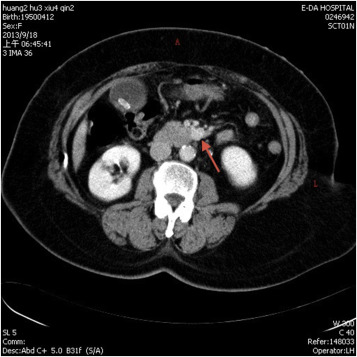

A 64-year-old woman with past medical history significant for hypertension had visited the emergency department many times over the course of several years due to intermittent hypertensive emergencies. On this presentation, she was admitted with features of symptomatic cholelithiasis. Abdominal ultrasound confirmed the presence gallstones and incidentally showed a 1.5-cm hypoechoic mass in the uncinate process of the pancreas (Figure 1 ). A physical examination was unremarkable except for mild right upper quadrant tenderness and elevated blood pressure (211/112 mmHg). Serum carcinoembryonic antigen and carbohydrate antigen 19-9 levels were both within normal limits. Contrast-enhanced computer tomography showed a 1.6-cm enhancing mass in the uncinate process of the pancreas (Figure 2 ). On magnetic resonance imaging, the lesion was identified as a 1.6-cm low-intensity mass on T1-weighted imaging and a slightly high-intensity mass on T2-weighted imaging. Magnetic resonance imaging with contrast enhancement revealed that the lesion was enhanced (Figure 3 ). On the basis of these findings, preoperative diagnosis was a pancreatic hypervascular tumor, suspected to be a neuroendocrine tumor. A pylorus-sparing Whipple procedure was recommended to achieve complete excision of the tumor and to treat the symptomatic cholelithiasis. Grossly, an oval and well encapsulated tumor measuring 1.5 cm in greatest dimension was noted within the lower part of uncinate process. Microscopically, this well-encapsulated tumor was composed of proliferation of polygonal cells arranged in trabecular, nest, and alveolar patterns separated by a stroma rich in vascular network. The tumor cells had an amphophilic-to-basophilic cytoplasm. Tumor nuclei were round to oval with moderate nuclear pleomorphism and prominent nucleoli (Figure 4 ). Mitotic figures were not identified. Capsular and vascular invasion was not present. By immunohistochemical staining, the tumor cells were reactive to CD 56, synaptophysin, and chromogranin A. The sustentacular cells surrounding the tumor clusters were also highlighted by immunostaining for S100. The lymph nodes dissected were free of malignancy. Both histomorphology and immunoprofiles of the tumor were typical of paraganglioma. Hypertensive urgency developed after the operation which was controlled with continuous intravenous nicardipine. Collected 24-h urine catecholamine data showed that norepinephrine levels were 175 μg/day (normal value: <97 μg/day) and vanillylmandelic acid levels were 8.06 mg/day (normal value: 1–7.5 mg/day). After 7-day nicardipine treatment, we gradually shifted to oral antihypertensive agents. Finally, the patient was successfully discharged with oral doxazosin (4 mg) one tablet per day. The patient had no clinical signs, symptoms, or family history suggestive of multiple endocrine neoplasia or Von Hippel–Lindau disease.

Figure 2. Axial contrast enhanced computed tomography abdomen demonstrated a 1.6-cm enhancing mass (arrow) in the uncus of the pancreas. |